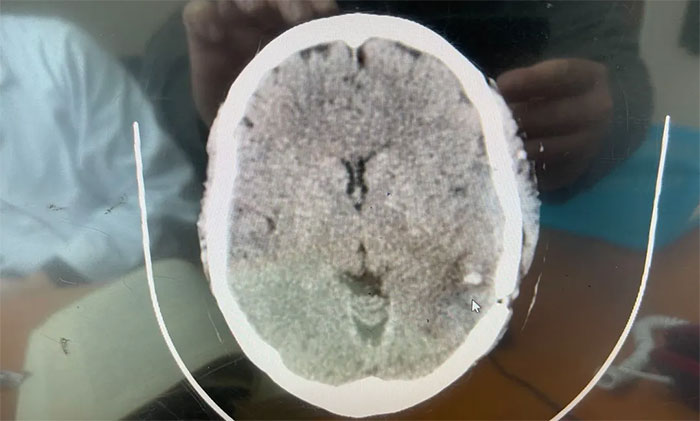

術(shù)后,患者頭部脹痛明顯緩解,睡眠狀況恢復(fù)良好。術(shù)后病理再次明確為顱內(nèi)海綿狀血管瘤。

▲術(shù)后CT示海綿狀血管瘤已被切除